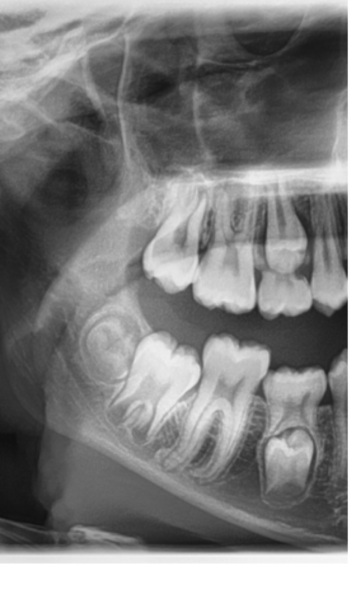

Just wondering if any dental people could help me understand this X-ray? Orthodontist letter says upper and lower E teeth both sides are retained. The lower E's need to be extracted then they'll look again when adult teeth are through.

I think I can see the unerupted teeth. Does the lower one look ok? It doesn't seem to have proper roots like the upper one does. Child is 12.5.

The roots on the lower premolar are just not formed yet , it’s quite normal.

Most times the adult teeth stimulate the baby teeth roots to be resolved, the baby tooth falls out and the adult tooth comes through.

Occaisionally, particularly on the es they get stuck and sometimes submerge and the adult tooth doesn’t come through. Normally taking the baby tooth out gets things going and the adult tooth comes through. I would think the upper tooth will come through quickly, the lower one , because it is further back in its development may take some time, I suspect the lower e is jammed against the tooth behind and is starting to submerge hence the delay.

Yes, lower premolar looks normal. And removing the retained baby teeth will get the adult teeth 'moving'. There is some resorption of the roots of the upper baby tooth, but the lower one looks like it could be a while. Possibly due to the position of the teeth around them etc

So it sounds like it's a good idea to get the baby teeth extracted then. I was just a bit unsure as although DD is 12 she's been quite late in all things tooth-related so it wouldn't surprise me if she's just a bit slow! But if the baby tooth is blocking normal development it needs to come out.

While I'm here, is that a wisdom tooth at the end?

on the lower jaw yes it is a wisdom tooth.